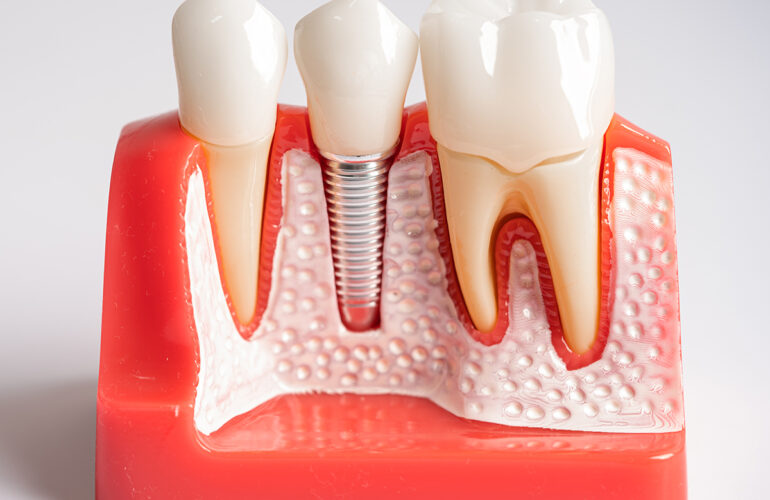

Le guide chirurgiche consentono di inserire l’impianto nella posizione ideale, con la massima stabilità.

• Risultati predicibili: posizionamento ideale dell’impianto.